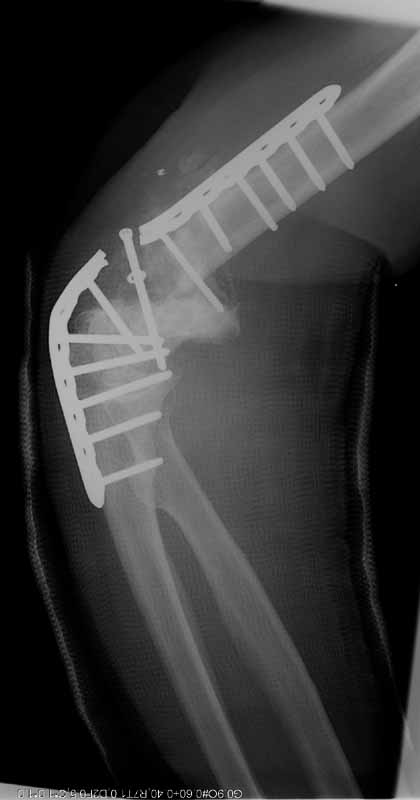

My fixation failed in January 2004. Please see attached files (first revision fail).

1st revision fail

At surgery it appeared infected. Cultures eventually grew out strep viridans subcultured through broth. It was very hyperemic. I treated it with hardware removal, a spanning plate that was meant to provide temporary stability, and irrigation & debridement x 2. (I did not use an external fixator because of the osteoporosis, and the inability to get stability of the fragments.) An antibiotic impregnated cement spacer was added. Files( after I&D.) Last I&D was in March 2004.

after I&D